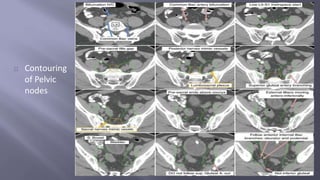

Pelvic LNs

Contouring

of Pelvic

nodes

Contind…

Contouring of Pelvic nodes Contind…